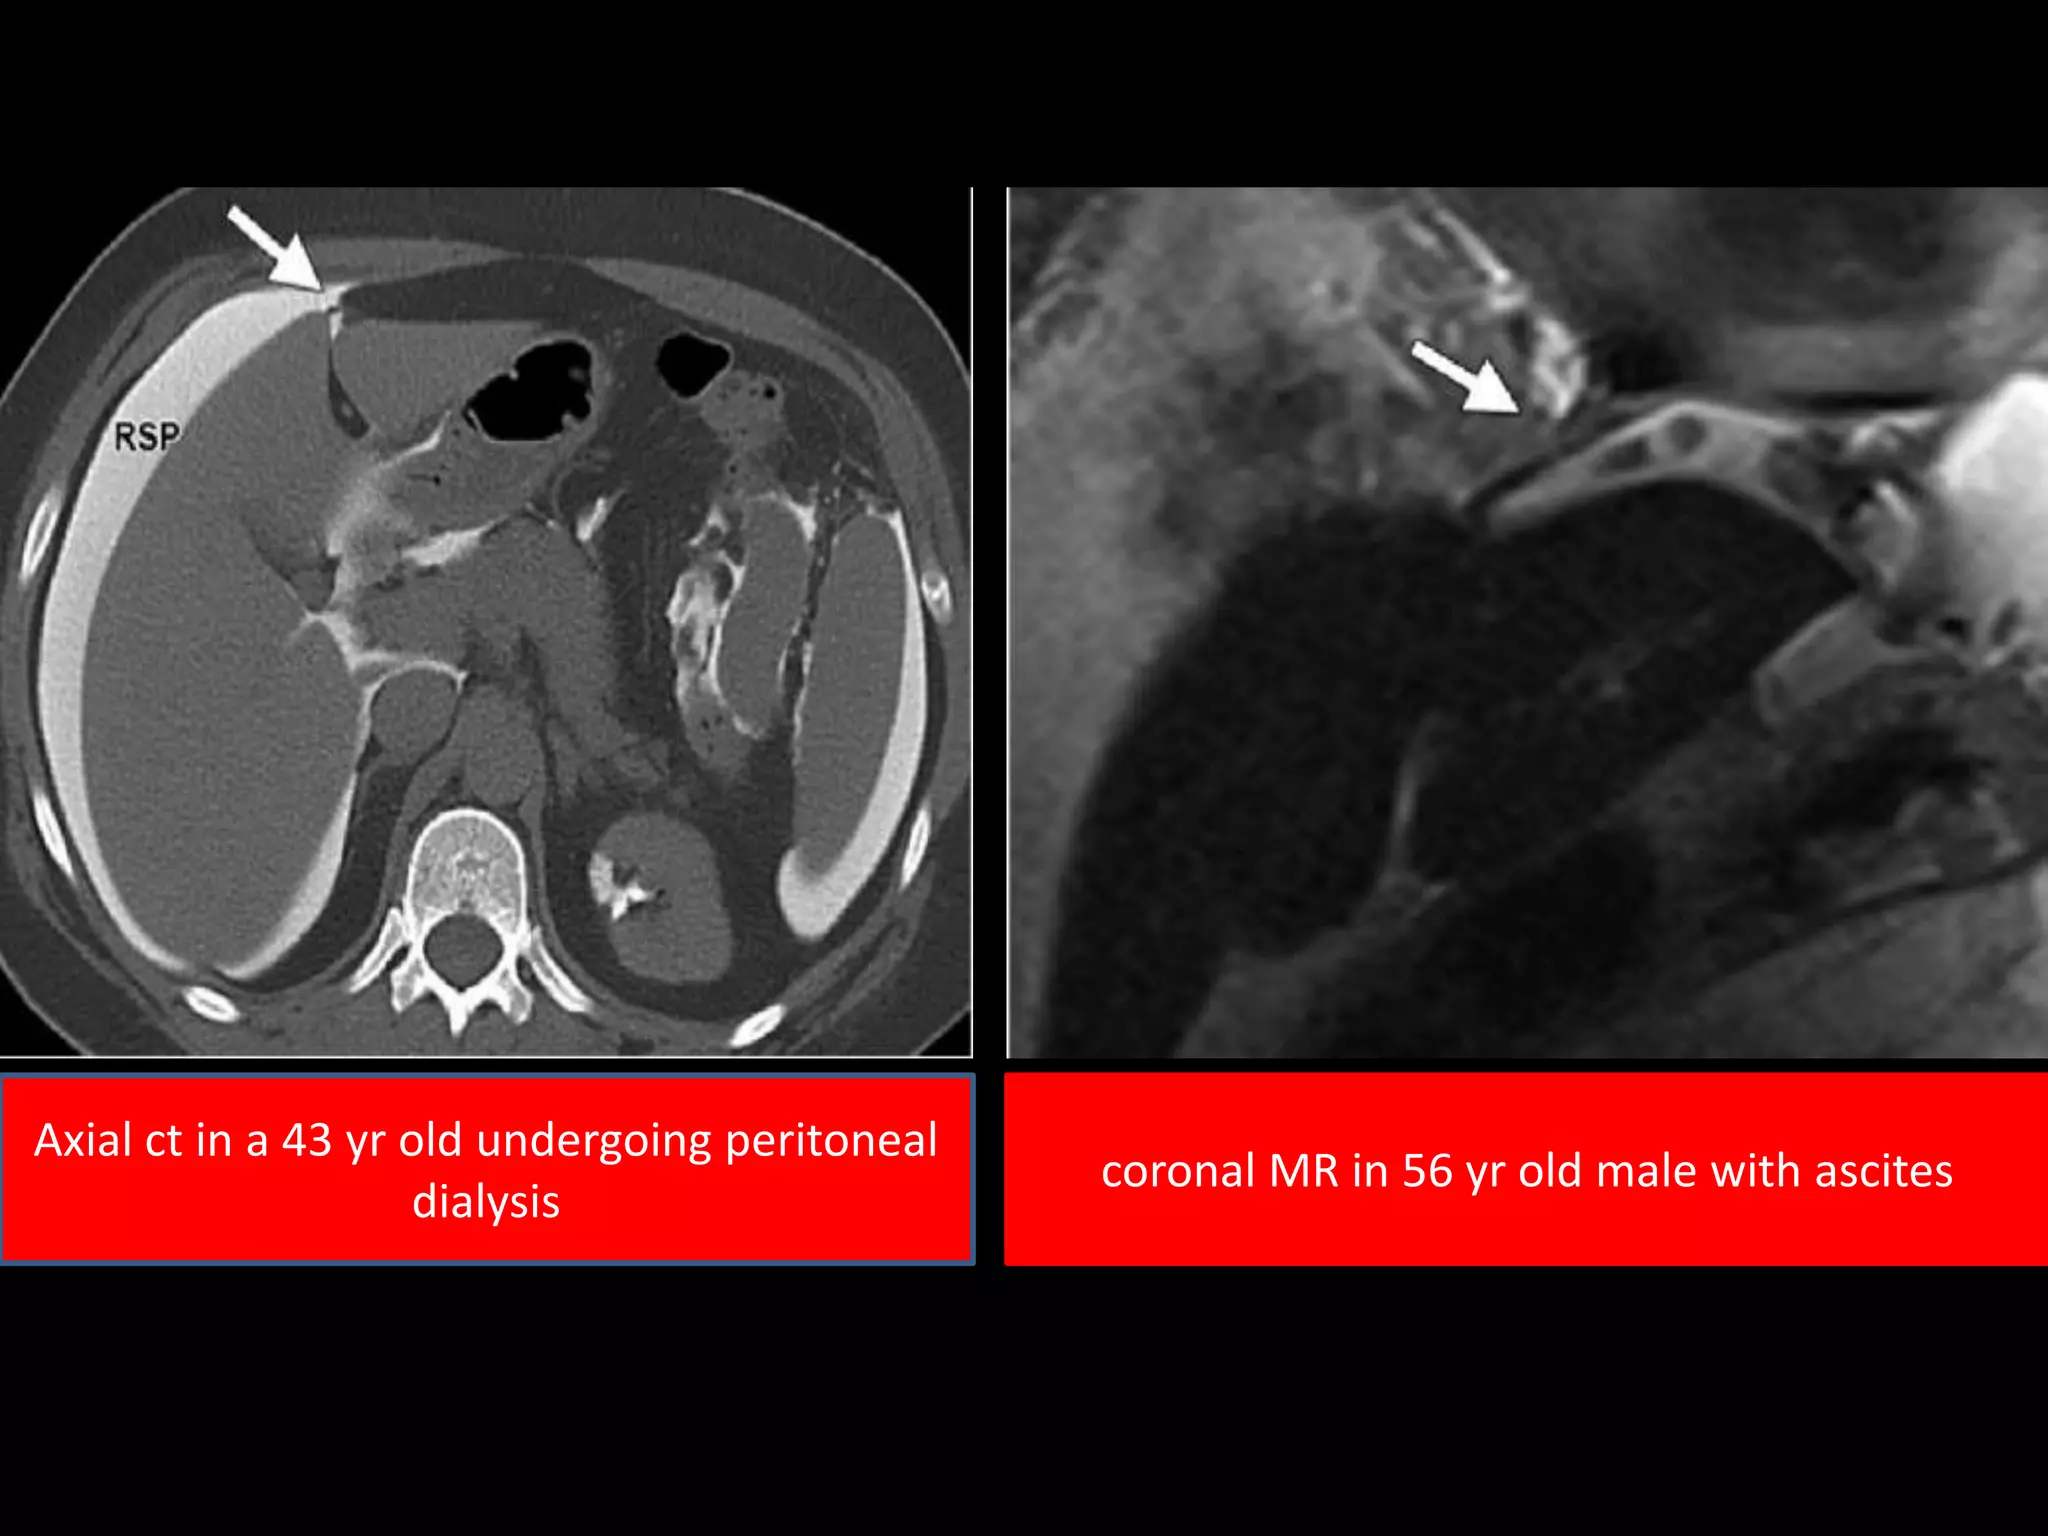

Axial ct in a 43 yr old undergoing peritoneal

dialysis

coronal MR in 56 yr old male with ascites